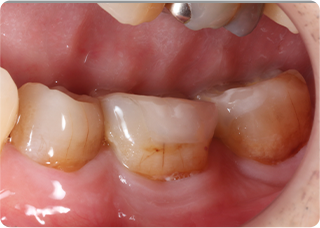

自家歯牙移植・精密根管治療・セラミッククラウン症例

術前

術後

| 主訴 | 奥歯の銀歯がぐらぐらして取れそう |

|---|---|

| 治療期間/回数 | 5ヵ月、10回 |

| 価格(税込) | 264,000円(税込) |

| リスク・副作用 | 生着不良、歯根吸収、骨性癒着の可能性 |

| ポイント | 銀歯の中でむし歯が進行し、保存不可能だったため抜歯し、後ろの親知らずを移植。移植の際に3Dプリンターで作製した親知らずのレプリカを使用し、治療時間の短縮と移植ポジションの確認を行った。生着するのを待ち、精密根管治療を行った後、セラミッククラウンを装着した。 |